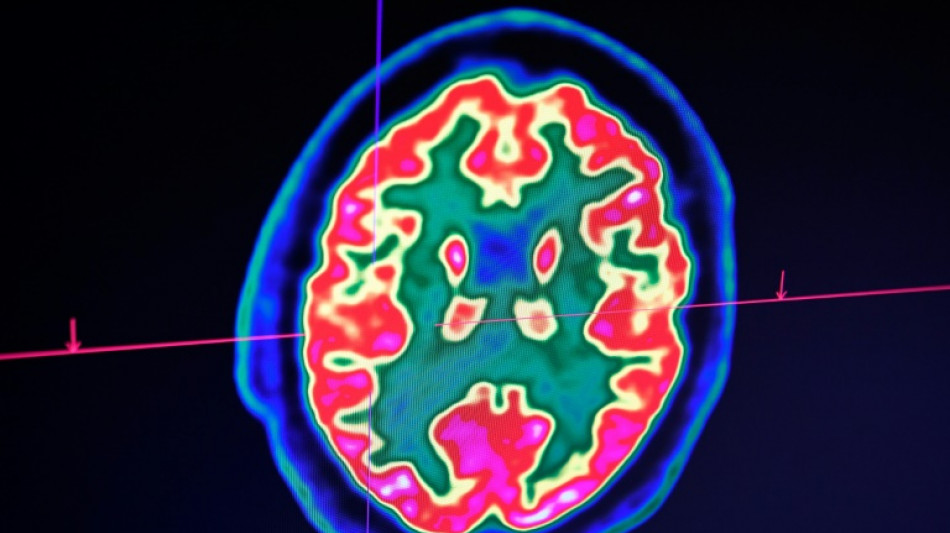

Cancer du cerveau: la guérison d'un enfant ouvre de grands espoirs pour la recherche

Cancer du cerveau: la guérison d'un enfant ouvre de grands espoirs pour la recherche / Photo: Fred TANNEAU - AFP

Rare mais fatal, le gliome infiltrant du tronc cérébral est l'une des formes les plus redoutables des cancers du cerveau pédiatriques. Un enfant, pourtant, semble défier les statistiques: sa guérison, unique au monde, suscite aujourd'hui de grands espoirs pour la recherche.